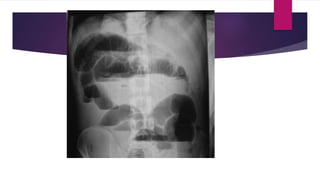

 Abdominal x ray – erect- ; multiple air fluid level

 abdominal xray - supine ; jejunanum –conniventose

; ileum- featureless

colon-haustral fold

investigations  Abdominal xray – erect- ; multiple air fluid level  abdominal xray - supine ; jejunanum –conniventose ; ileum- featureless colon-haustral fold CECT ABDOMEN